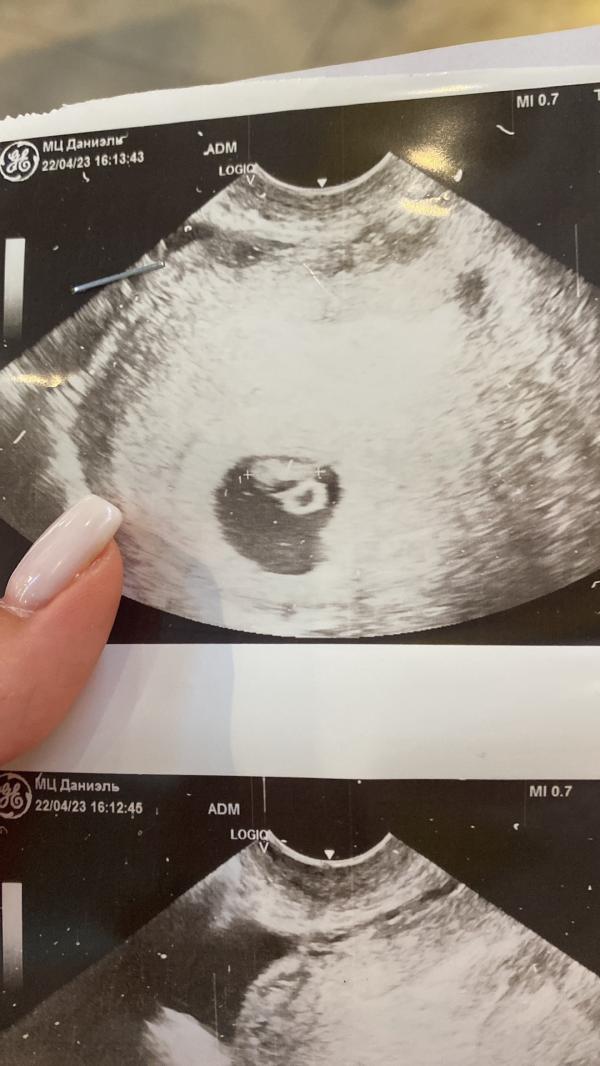

*наш Крошка на фото узи🥰

ТАК ОНО И ПРОИЗОШЛО!

Мы верили, и оно случилось!

Врач смотрит и говорит «вижу плодное яйцо в матке, но эмбриона в нем нет😳 вероятно у вас анэмбриония, потому что на этом сроке уже должно быть видно эмбрион»

После чего врач сказала приходить еще через 2 недели на сердцебиение, и если не будет ничего видно/слышно, то поставят ЗБ и отправят на чистку…